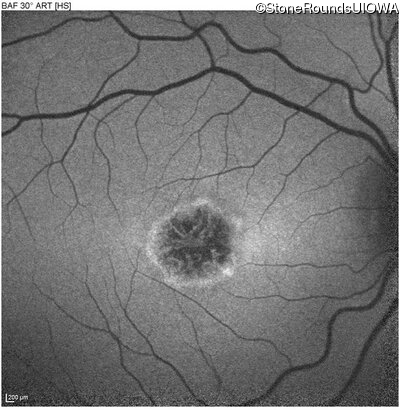

Blue Autofluorescence - Right - 20/125 sc

Exemplar